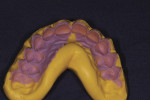

The mesiodistal width of teeth Nos. 8 and 9 was 9 mm. Thus, their ideal length had to be close to 11.2 mm.2,6 This value was used as a guideline to mark a point on the gingival tissues at 11 mm from the incisal edges of mocked-up teeth Nos. 8 and 9 on the stone model. The proposed gingival outline was prepared on the stone model from teeth Nos. 4 though 13. A mock gingival surgery was performed on this cast (Figure 6), and an index was made over it with silicone putty and light-body material. The gingival outline of this silicone putty was trimmed precisely along the scallop of the proposed gingival outline from teeth Nos. 4 though 13. This would now be used as a surgical guide (Figure 7) by the periodontist.

Three weeks later, a full-contour wax-up (Figure 10) with “prep”’ guides and a clear silicone index fabricated on the waxed-up model were received. This silicone index would be used to carry material onto the teeth for direct fabrication of provisionals intraorally.